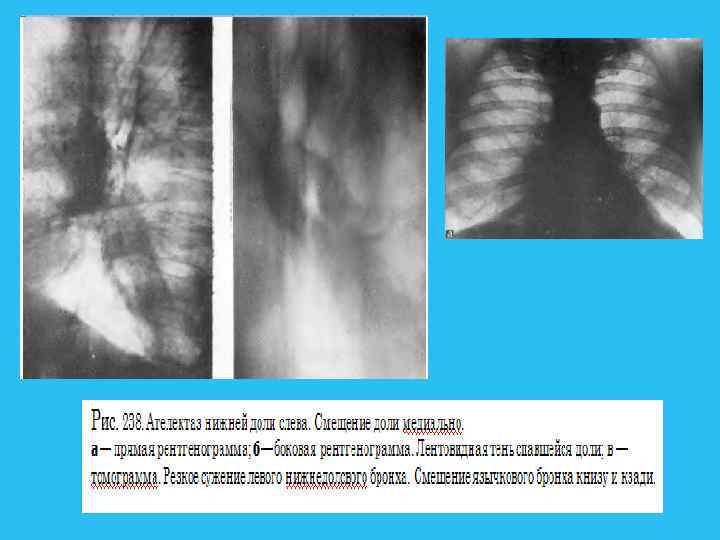

Ателектаз развивается при полной обтурации бронха опухолью, характеризуется полным рассасыванием воздуха из легочной ткани и резким ее объемным уменьшением. Кроме этих прямых признаков, как и при дистелектазе, большое диагностическое значение имеют вторичные симптомы, в той или иной степени сопутствующие ателектазу. Это, в первую очередь, смещение междолевой плевры и ее вогнутость в сторону объемного уменьшения. Выявляются также смещение корня легкого к ателектазу, средостения в сторону поражения, подъем купола диафрагмы и сужение межреберий на больной стороне, викарная эмфизема прилежащих участков легкого. Эти признаки также неспецифичны и указывают на объемное уменьшение легкого. В ателектазе также часто развиваются воспалительные и деструктивные изменения. Диагностировать их не всегда удается, лишь в отдельных случаях развиваются полости с газом и уровнями жидкости. Признаком тяжелой, обширной гнойной деструкции в ателектазе является нормальный размер доли или даже ее объемное увеличение такие случаи требуют неотложной хирургической помощи. При формировании ателектазов сегментов, долей соблюдаются определенные правила, знание которых облегчает топическую ориентировку и сокращает диагностический поиск. Во первых, любой ателектазированный участок смещается медиально и обязательно связан с корнем легкого. Во вторых, тень ателектаза смещается туда, где в норме располагались до этого сегмент или доля. В третьих, все доли и сегменты, граничащие с междолевой плеврой, в определенных проекциях обязательно сохраняют четкость очертаний. Участки же, не соприкасающиеся с плеврой, в любой проекции имеют размытый контур. Кроме медиального направления, доли спадаются следующим образом:

справа верхняя вверх и вперед, средняя вперед, нижняя вниз и кзади; слева верхняя вперед, нижняя вниз и кзади. Напомним сегменты, граничащие с междолевой плеврой: справа в верхней доле S 2 и S 3 , нижней S 6, S 7, S 8, слева в верхней S 1 2, S 4 и S 5, нижней S 6 и S 8. Оба сегмента средней доли ограничены междолевой плеврой. При формировании ателектазов междолевая плевра часто значительно изменяет свое положение и выявляется в проекциях, перпендикулярных тем, в которых она видна в норме. Например, при ателектазе средней доли горизонтальная междолевая плевра прослеживается только в боковой проекции, при ателектазе S 6 с обеих сторон (особенно часто слева) косая междолевая плевра отчетливо видна в прямой проекции. Сочетание ателектазированных долей и сегментов указывает на пораженный бронх, но не всегда эта зависимость соблюдается в полной мере. При резком стенозировании просвета бронха может не быть признаков нарушения вентиляции ткани легкого. И наоборот, при четко видимом просвете может сформироваться дистелектаз паренхимы. Такой вариант особенно характерен для рака Б 1 2 слева, часто имеющего перибронхиальный стелющийся рост и сопровождаемого симптомом "удлинения бронха".

Некоторые виды ателектазов носят "скрытый" характер и для их выявления требуется внимательность, опыт и соблюдение методик обследования. В первую очередь, это ателектаз нижней доли слева, который "прячется" ретрокардиально и проявляется в прямой проекции лишь дополнительным паракардиальным контуром. Не видна порой в прямой проекции ателектазированная средняя доля, зато не заметить ее на боковом снимке невозможно. Бывают случаи, когда на фоне ателектаза, дистелектаза или обтурационной пневмонии определяются просветы мелких бронхов на большом протяжении. Выявление такой воздушной бронхограммы может быть причиной роковой диагностической ошибки. Этот симптом считается патогномоничным для воспалительных процессов в легких, особенно популярен при КТ диагностике. Однако для воспалительных процессов неукоснительно соблюдается следующее правило воздушная бронхограмма должна быть прослежена на всем протяжении, от главного, долевого бронхов до мелких ветвей. Если есть участки прерывания просвета бронхов, то в первую очередь следует думать о центральном раке. Полный ателектаз доли, легкого часто не позволяет определить истинные размеры опухолевого узла в корне. В силу их одинаковой плотности даже КТ без контрастирования не поможет в таких случаях, и лишь КТ с болюсным усилением иногда может дать возможность дифференцировать ателектаз от опухоли. На фоне ателектаза не следует пытаться искать очертания опухоли или лимфоузлов, так как истинные контуры в легких формируются не границе двух тканей воздушной и безвоздушной (то есть мягкотканной плотности).